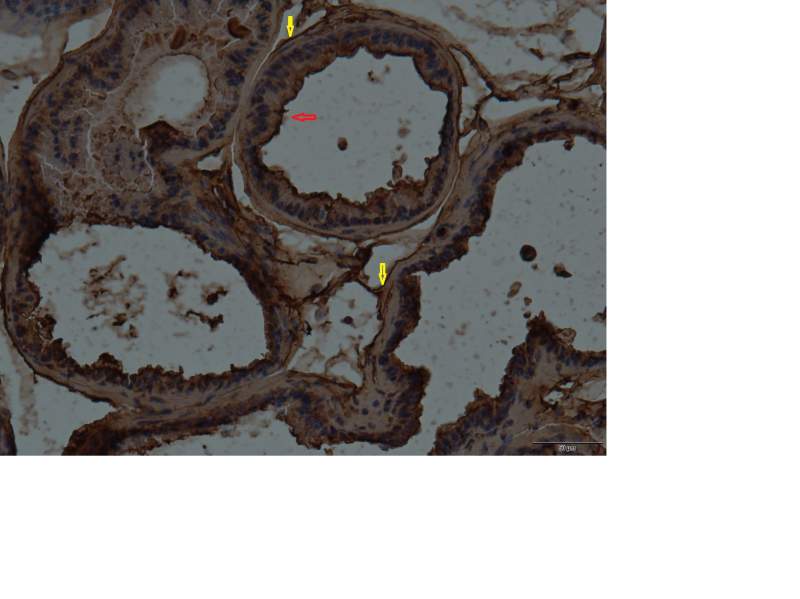

如附件中所示 是我做的正常小鼠前列腺组织的IHC切片 20倍放大 我用的是PI3K β抗体 如图中三个箭头处 我感觉红色箭头 处像是染上抗体 但是黄色箭头处不知道是什么 还请大侠不吝赐教 多谢啊 474 p110b lateral lobe 20.jpg |